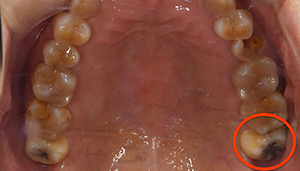

- 口腔内写真

| 治療方針 | 左上の親知らずをみてみると虫歯になっており、真っ黒になっていました。 そのため、虫歯治療ではなく、抜歯を行うことにしました。 |